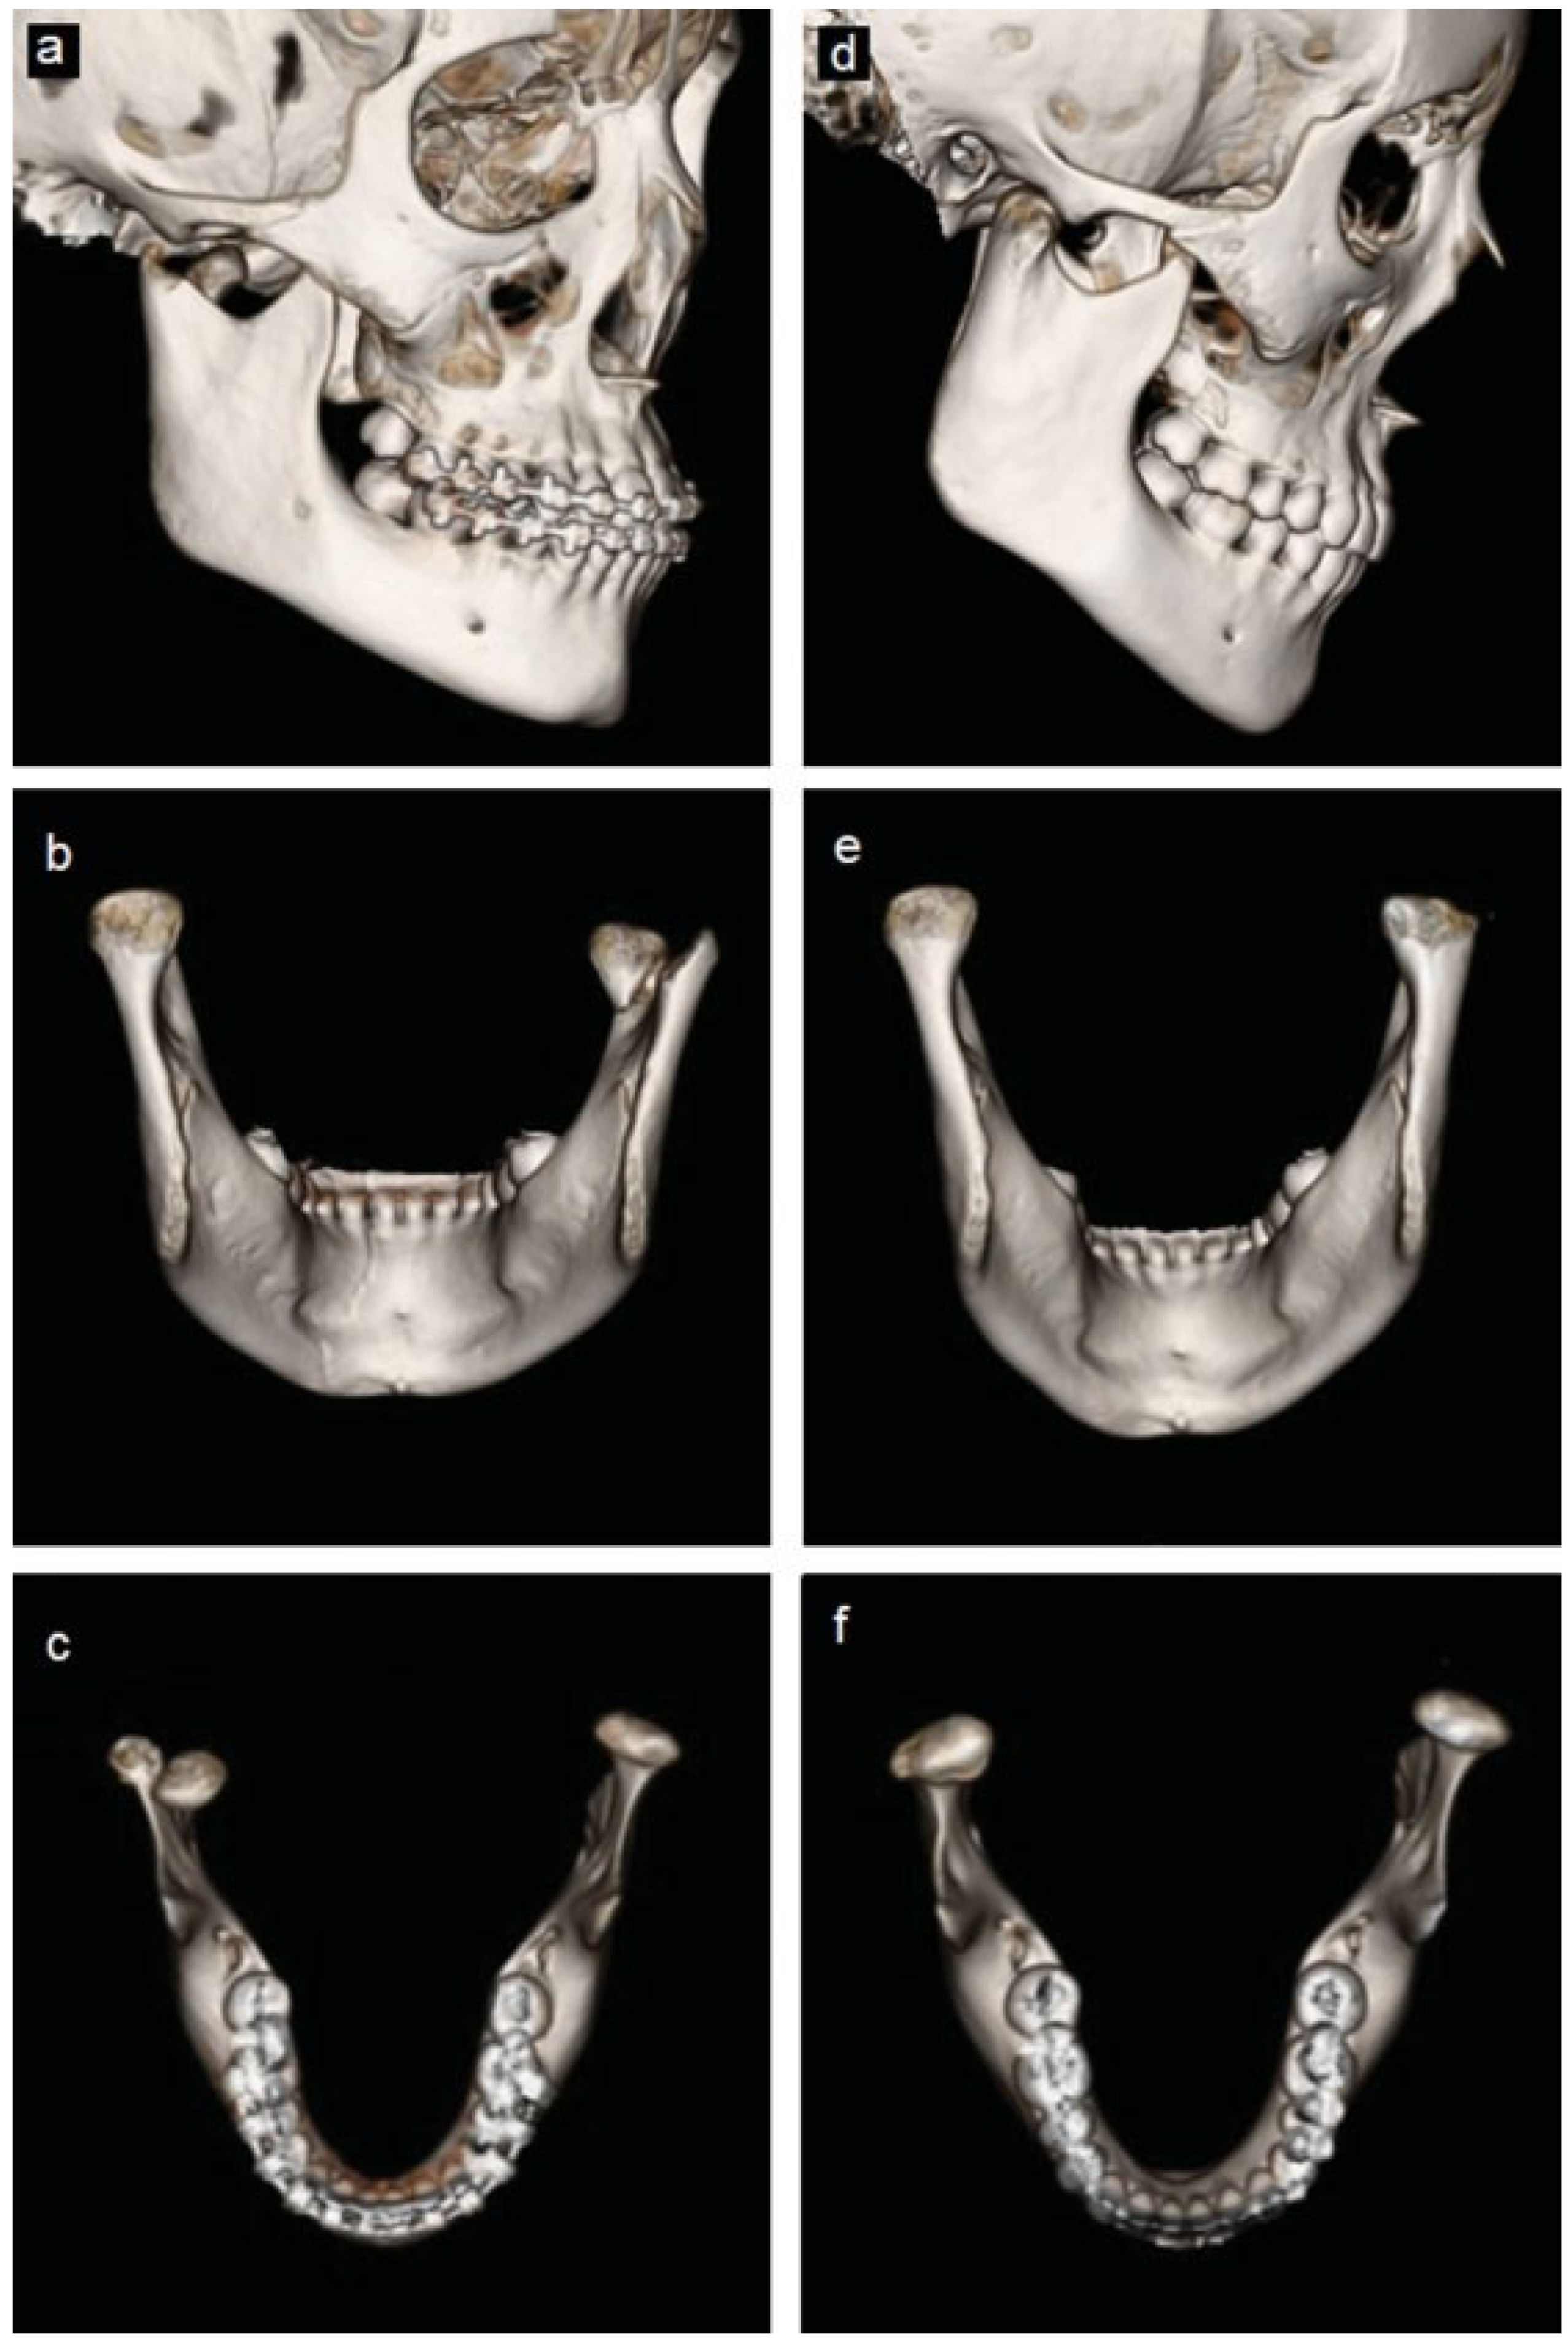

The second patient, a healthy 21-year-old male patient presented to the emergency department at another health institution after being involved in interpersonal violence and falling on his chin. He suffered a right-sided displaced and left-sided nondisplaced condylar neck fractures and a displaced mandibular symphysis fracture. A CT scan was taken (Figure 3a–c and Figure 4a–c). The patient underwent open reduction and internal fixation of the symphysis fracture; and nonsurgical treatment of the bilateral condylar fractures with placement of Erich arch bars and intermaxillary elastics with light function.

The patient was first seen at our clinic for a follow-up evaluation 6 months after the initial treatment. At this time he had regained full mandibular function and denied myofascial or TMJ symptoms. He also denied limitation of motion, noise with TMJ function, and was tolerating a normal diet. His occlusion was a stable class I with good interdigitation. There was an excellent range of motion with slight deviation to the right with wide opening. There was no myofascial pain or joint pain with occlusal loading. A CT scan was obtained due to concerns by his previous physician regarding the possible need to surgically reposition the previously displaced condyle d–f and Figure 4d–f). This CT scan showed reformation and repositioning of the right condyle with normal cortical and cancellous anatomy but with a slight anteroinferiorly displaced position with associated mild flattening of the condylar head. Additional treatment was not advised.

Figure 4. (ac) Comparison between pre-treatment and (df) 6-month posttreatment 3D reconstructed computed tomography of patient 2. Displacement of the fractured right condyle is well-visualized in pretreatment images as well as the subsequent remodeling that has taken place resulting in a flattened and slightly anteroinferiorly positioned condyle in the posttreatment images.